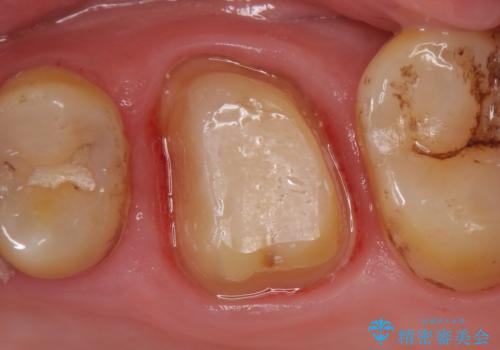

診査の結果、左上6が失活(歯の神経が死んでいる状態)しており根尖病変を認めたため、根管治療を行いました。

根尖病変の縮小及び症状の消失を確認後、オールセラミッククラウンによる補綴を行いました。